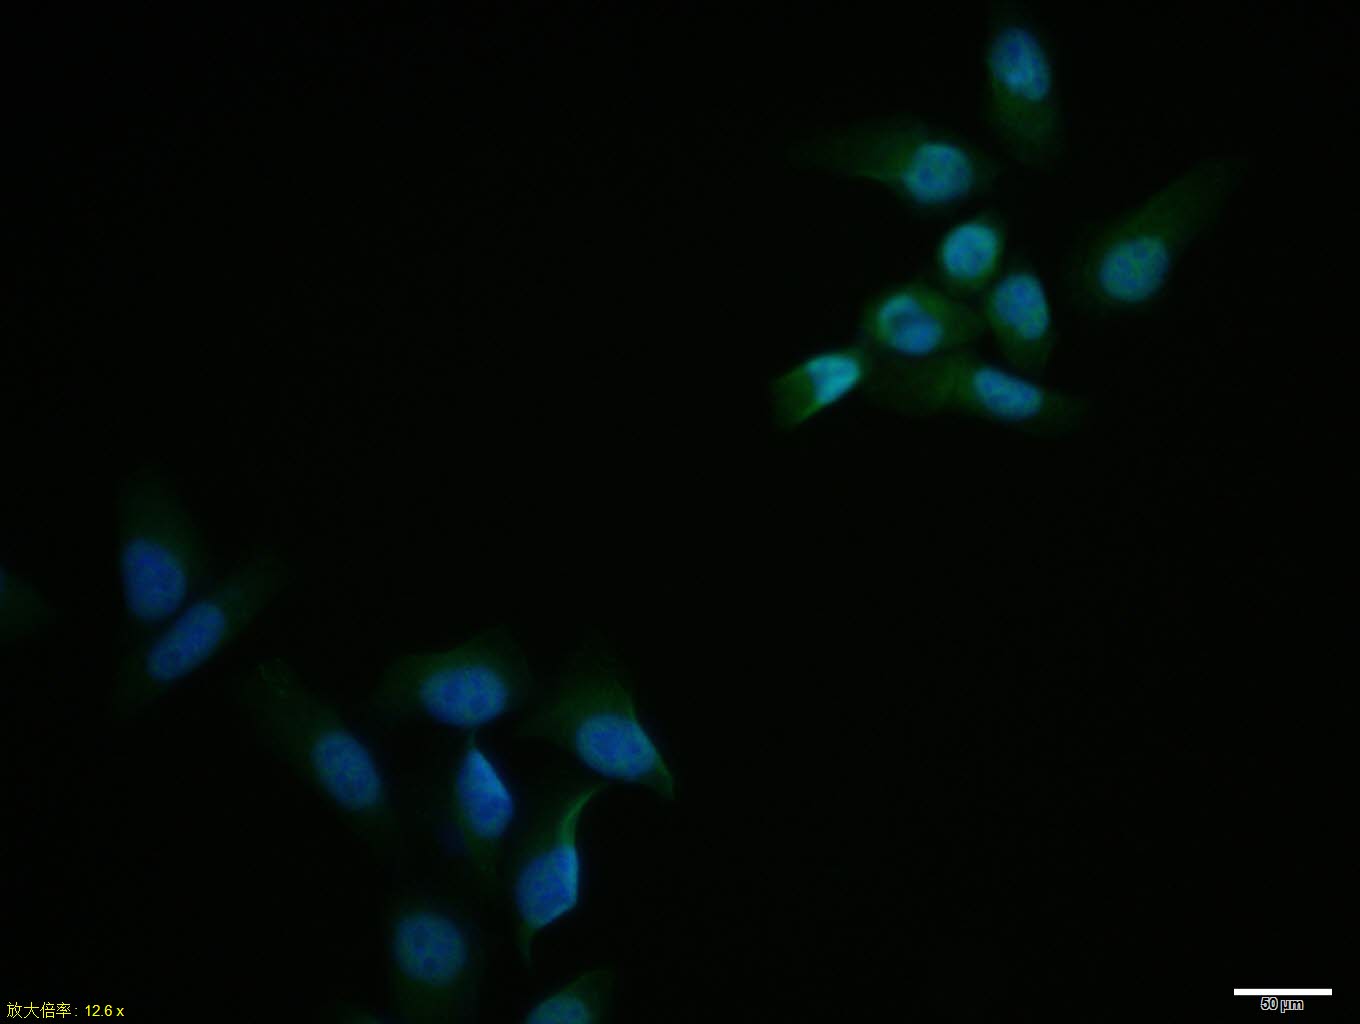

Hela cell; 4% Paraformaldehyde-fixed; Triton X-100 at room temperature for 20 min; Blocking buffer (normal goat serum, C-0005) at 37°C for 20 min; Antibody incubation with (MAPK4) polyclonal Antibody, Unconjugated (bs-1319R) 1:100, 90 minutes at 37°C; followed by a conjugated Goat Anti-Rabbit IgG antibody at 37°C for 90 minutes, DAPI (blue, C02-04002) was used to stain the cell nuclei.

Blank control:Hela. Primary Antibody (green line): Rabbit Anti-MAPK4 antibody (bs-1319R) Dilution: 2ug/Test; Secondary Antibody : Goat anti-rabbit IgG-FITC Dilution: 0.5ug/Test. Protocol The cells were fixed with 4% PFA (10min at room temperature)and then permeabilized with 90% ice-cold methanol for 20 min at -20℃.The cells were then incubated in 5%BSA to block non-specific protein-protein interactions for 30 min at room temperature .Cells stained with Primary Antibody for 30 min at room temperature. The secondary antibody used for 40 min at room temperature. Acquisition of 20,000 events was performed.